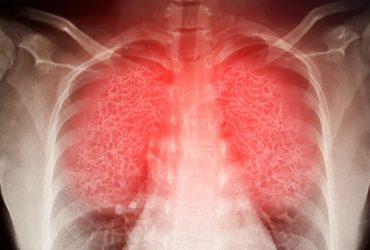

Seven graded recommendations and nine ungraded consensus statements developed for lung cancer screening